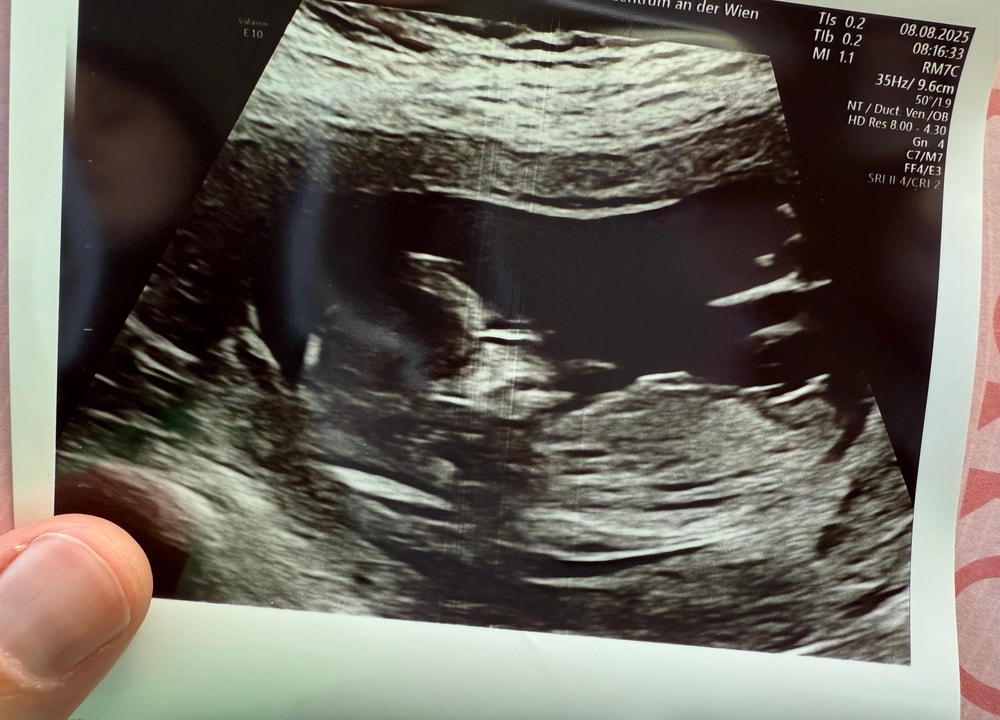

Девочки Перенесли 2х эмбрионов,как думайте 1-2 два?☺️делитесь своими хгч ☺️сколько у вас было примерно 10-14дпп

Потихоньку радуюсь🙈очень надеюсь будет победный 8-перенос наш☺️